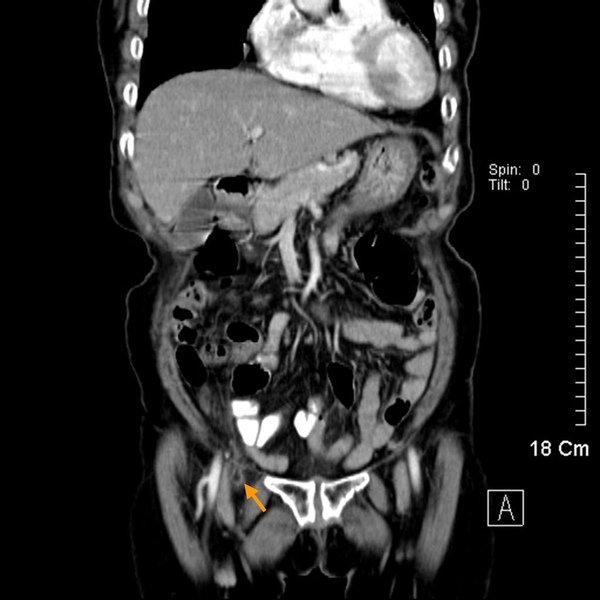

下面這張圖有點兒複雜,先看到黃色虛線,這大約是腹股溝韌帶(Inguinal ligament)的所在。在腹股溝韌帶上方,可以見到精索(黃色箭頭),這個位置也是方才提到腹股溝疝氣的位置。在腹股溝韌帶(Inguinal ligament)下方,正常時候只可見到股動脈(Feomral artery)、股靜脈(Femoral vein),圖中橘色箭頭多出來的部分便是股疝氣。

下圖可以見到股靜脈內側,橘色箭頭處,凸出的一塊,這便是股疝氣。這個位置周圍被韌帶及骨頭包圍,空間有限,所以股疝氣一般尺寸不會太大。卻也因為入口處狹窄堅固,便容易導致嵌頓。